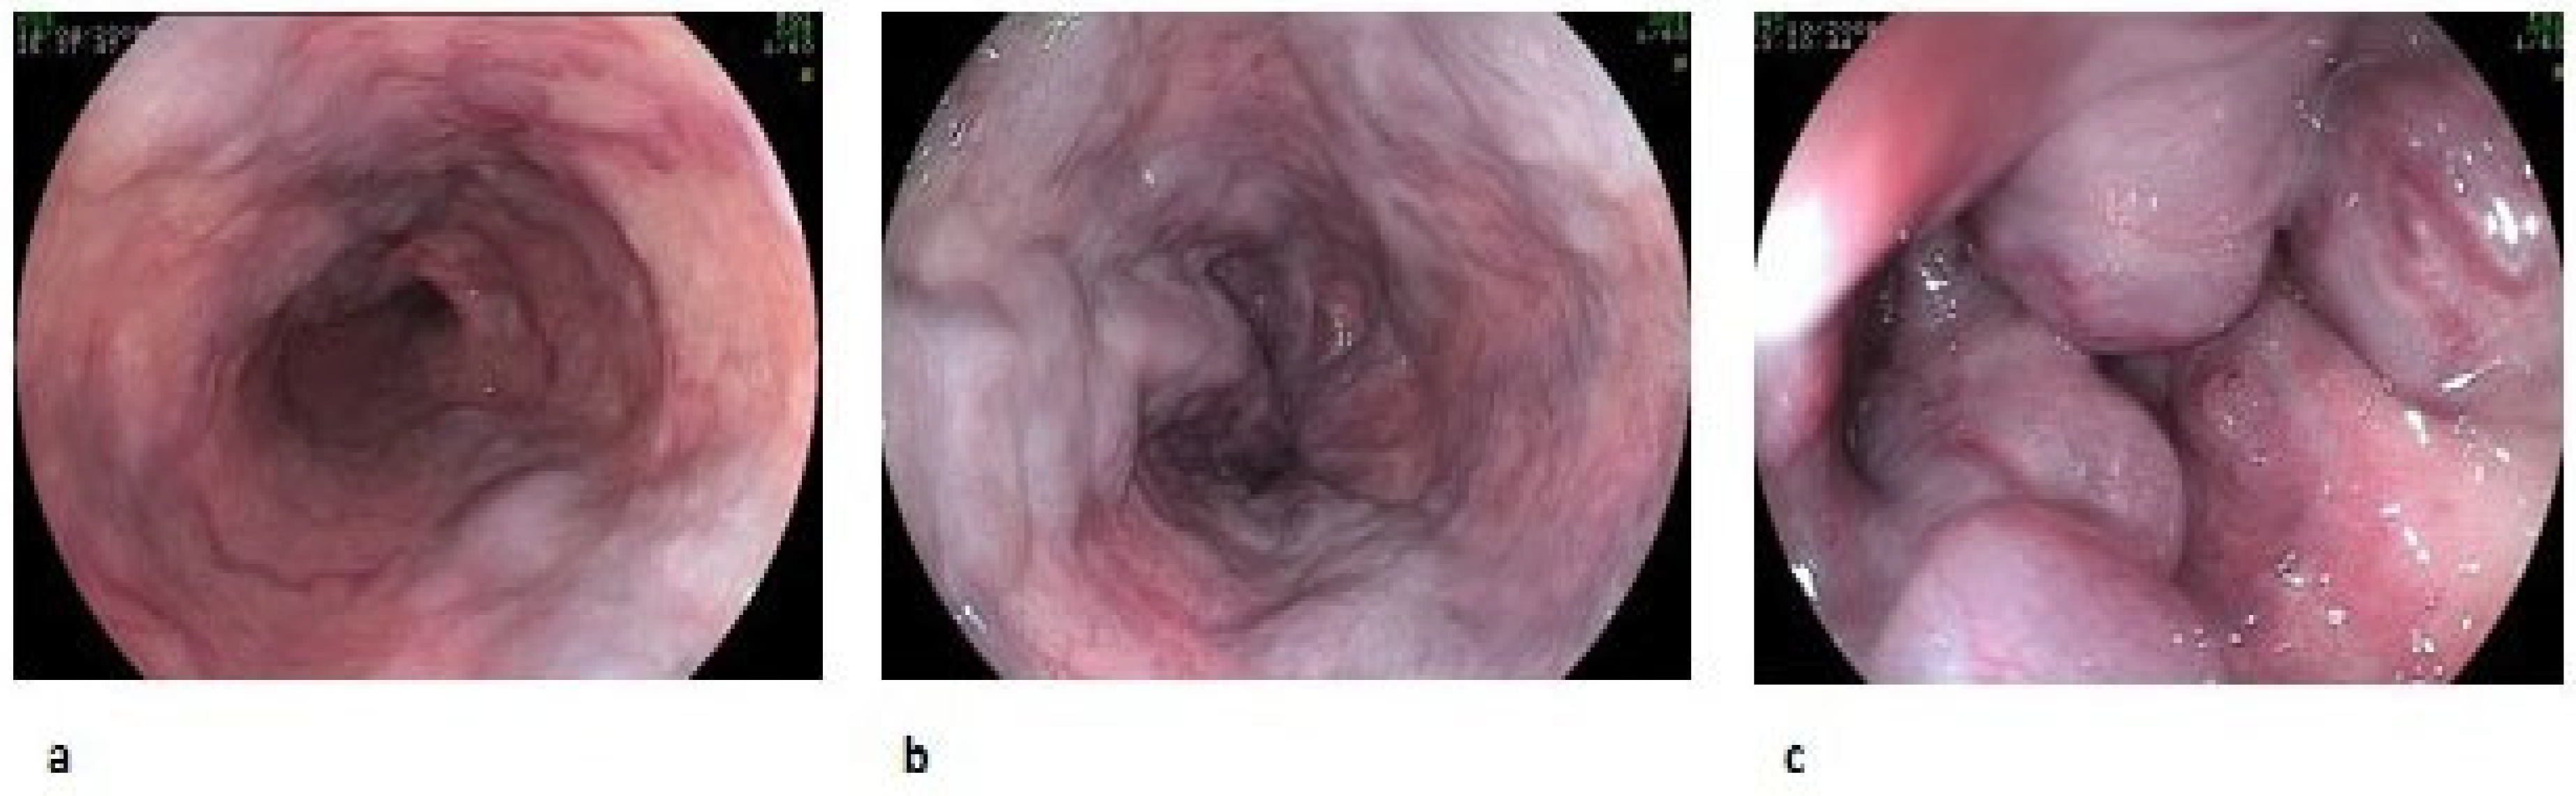

| Form | F1: straight-shaped varices (do not disappear with insufflation) F2: slightly enlarged tortuous varices occupying less than one-third of the esophageal lumen F3: large-sided varices occupying more than one-third of the esophageal lumen |

| Fundamental color | White (CW) Blue (CB) |

| Red color sign (RC) | Red Wale Marking (RWM) Cherry Red Spot (CRS) Hematocystic Spot (HS) Diffuse Redness (DR) |